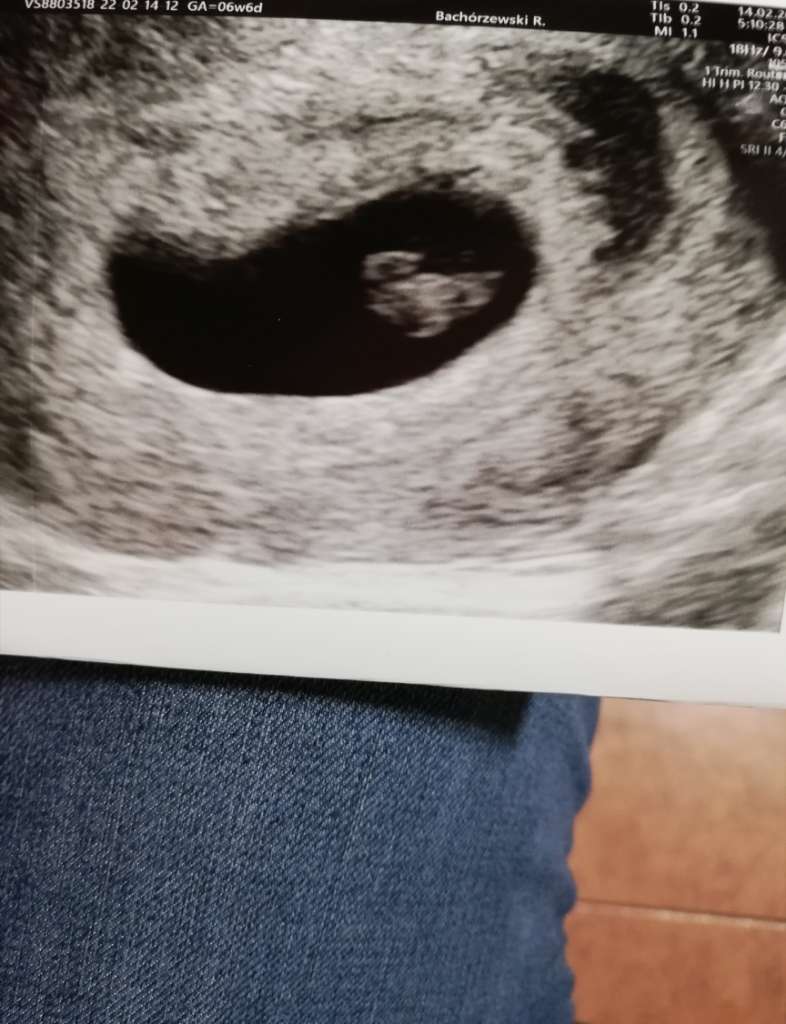

A tu zdjęcia z dziś 😍

Załączniki

• 2cc92550-dea5-4b95-9262-be4bbf93084c.jpg

2cc92550-dea5-4b95-9262-be4bbf93084c.jpg

71,6 KB · Wyświetleń: 99

tak, 6t6d. Ma wielkość 1,06cm 😉 mój ginekolog faktycznie ma dobry sprzęt 🙂 pewnie i u Ciebie będzie widac już co nie co😉który to będzie tydzień?